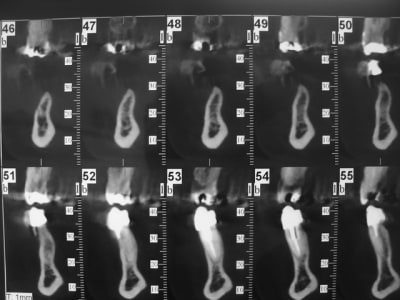

coupe_secteur_3_akuiru.jpg

coupe_sect_4_c0hkw3.jpg